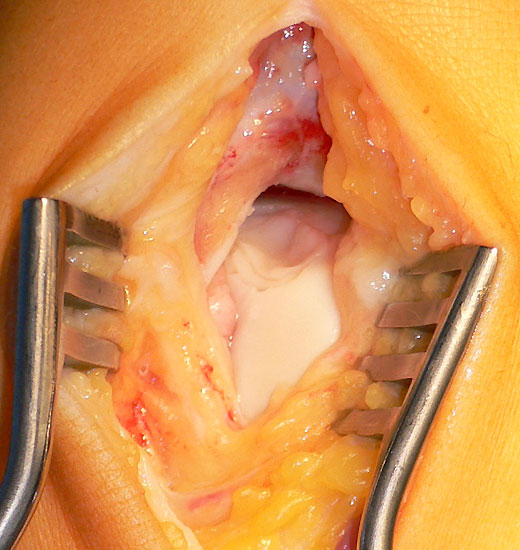

Debridement des Defektes und anterograde stimulierende Techniken

Bei chondralen Läsionen III-IV° oder bei osteochondralen Läsionen (≥ Stadium 2) mit Kontinuitätsunterbrechung der Knorpeloberfläche und Instabilität des Fragmentes (Abb. 11), besteht in der Regel die Indikation zum Debridement und Kürettage der Läsion und Anwendung von knochenmarkstimulierenden Techniken wie der Anbohrung oder Mikrofrakturierung. Durch die chirurgische Eröffnung des subchondralen Knochens sollen über die gesetzten Blutungsherde pluripotente mesenchymale Stammzellen in die Defektzone gelangen und einen Reparaturprozess einleiten 52. Ziel ist die Bildung eines möglichst belastungsstabilen Ersatzknorpelgewebes. Das arthroskopische Vorgehen mit Knochenmarkstimulation stellt nach einem Expertenkonsensus während der „Conference of the International Society of Arthroscopy, Knee Surgery and Orthopaedic Sports Medicine and International Federation of Sports Medicine (ISAKOS—FIMS)” aus dem Jahre 2005 für die meisten Fälle die Methode der ersten Wahl dar 39. Bevorzugt wird heute meist die Mikrofrakturierung, bei der rein arthroskopisch nach Stabilisierung der Läsion mit Schaffung intakter Knorpelkanten mit verschieden abgewinkelten Ahlen multiple Löcher unter Erhalt von Knochenbrücken in das Defektbett geschlagen (Abb. 12 und 13) und so eine Verbindungen zum spongiösen Knochen hergestellt wird. In der Regel können die Läsionen mit den arthroskopischen Standardportalen behandelt werden 5354. Orientierend kann bei der Planung und physiologischer uneingeschränkter Plantarflexionsmöglichkeit angenommen werden, dass neben den anterioren Defekten auch Läsionen, welche die vordere Hälfte des posterioren Anteil des Talus betreffen, erreicht und rein arthroskopisch behandelt werden können 39. Im Zweifelsfall kann eine Bildgebung in maximaler Plantarflexion weitere Hinweise geben.

Eine Verbesserung der Ergebnisse in Zusammenhang mit Durchführung einer Mikrofrakturierung v.a. bei größeren Defekten könnte eventuell durch Aufbringen von zellfreien Membranen (z.B. Kollagenmembran) erreicht werden. Für diese Verfahren wird auch der Begriff „AMIC“ (Autologe Matrixinduzierte Chondrogenese) verwendet. Ziel ist das durch die Mikrofrakturierung ausgetretene Blut besser im Defekt zu halten und eine verbesserte Regeneratstruktur zu erreichen. Bis auf die Beschreibung der Technik und einen Fallbericht sind allerdings noch keine Ergebnisse dieser Technik publiziert 46. Kontrovers wird diskutiert, ob ein offenes Vorgehen gewählt werden muss, oder ob auch ein arthrokopisches Vorgehen möglich ist. Hauptunterschied ist, dass beim offenen Vorgehen die Membran perfekt auf den Defekt zugeschnitten wird, während beim arthroskopischen Vorgehen dies nicht möglich ist und die Membran die Defektränder nach dem Einbringen überlappt. Beim offenen Vorgehen können vorhandene zystische subchondrale Veränderungen oder lokale Knochennekrosen durch vollständige Ausräumung der Läsion, Anbohrung der Randzone und Spongiosaauffüllung besser adressiert werden. Die Kollagenmembran wird mit Fibrinkleber passgenau in der Defektzone fixiert (Abb. 14). Die arthroskopische Implantation der Kollagenmembran ermöglicht ein weichteilschonendes Vorgehen ohne Notwendigkeit einer Arthrotomie oder Osteotomie der Malleolen. Die Indikation besteht aufgrund der einfachen Anwendbarkeit und des Vorteils einer Art Versiegelung des Defektes durch die Membran bei Defektgrößen > 1cm². Durch Bewegung werden die über den Defektrand überstehenden Bereiche der Membran abgerieben. So entsteht eine perfekte Deckung der subchondralen Schicht (Abb. 15). Die Kollagenmembran wird mit Hilfe einer Moskitoklemme redundant überlappend im Sinne einer Versiegelung auf den Defekt gelegt (Abb. 16) und mit einem Tasthaken anmodelliert (Abb. 17). Bei tieferen Defekten wird evtl. eine Doppelung der Kollagenmembran im Sinne einer Sandwichtechnik vorgenommen, um somit eine größere Oberfläche zu erreichen.